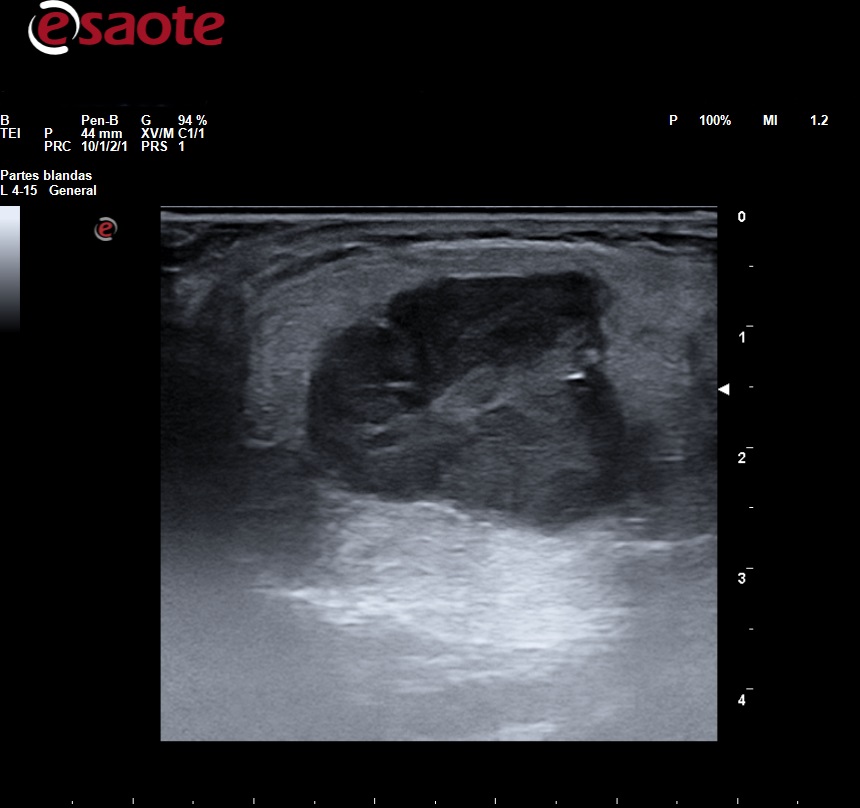

Observamos en la parótida una lesión sólida de 2,5 cm en su eje mayor, hipoecoica, heterogénea, lobulada con refuerzo acústico posterior, Doppler color presentaba vasculación escasa.